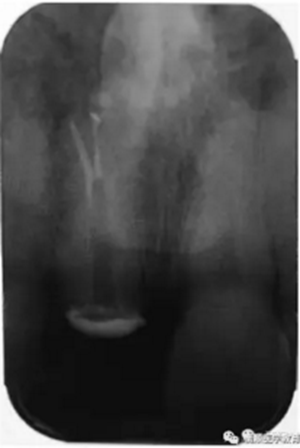

基于臨床檢查和X線片顯示,診斷為右上頜中切牙根尖周炎伴額外牙。治療計劃是先行患牙的根管治療,制作臨時義齒,最后制作樁核冠。應用橡皮樟和顯微根管技術,利用ProTaper旋轉銼配合使用 Hedstrom 銼和桉葉油,將根管內充填物取出,觀察X線片可見根尖三分之一處主根管一分為二,確定另一根管的工作長度,兩根管同行常規(guī)根管治療,充填后X線片顯示根管充填良好。樁核冠修復1年后,患牙無疼痛,影像檢查發(fā)現根尖顯影正常,根尖疾病治愈。

圖2. 患牙根管充填后即刻X線片顯影